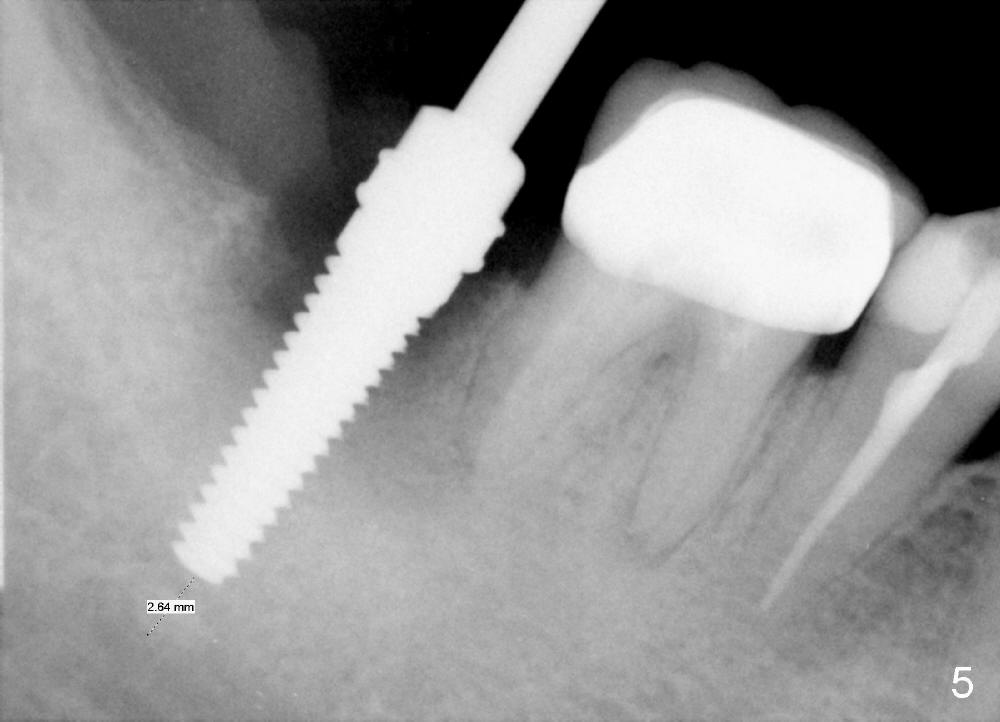

A 51-year-old man has experienced pain and swelling in the lower right 2nd molar for 7 months (Fig.1, P: post in the mesial root; <: gutta percha inserted into a buccal fistula). Fig.2 is taken immediately before extraction (<: purulent discharge from the mesiobuccal fistula) and immediate implant (Fig.3 implant design: 7x14 mm). A vertical root fracture is noted in the mesial root (Fig.4: lingual view). The septum is in fact absent, as compared to Fig.1. The mesiobuccal plate is low; the osteotomy starts lingual to the center of the socket. Fig.5 shows a 4.5x17 mm tap in place: approximately 3.5 mm in the new bone (~2.5 mm from the inferior alveolar canal). When a 7x17 mm tap (14 mm from the gingival margin) is placed in the socket, it looks relatively small. Fig.6 shows a 8x14 mm implant in place with a small gap distally. Mineralized cancellous allograft and Osteogen mixture is placed mainly buccally, followed by a thin strip of collagen dressing and sutures (Fig.7); an abutment (A) is placed to keep perio dressing in place. The perio dressing does not stay long. The buccal portion dislodges by itself 5 days postop. The lingual portion is removed in clinic. New dressing is going to be re-applied, because the buccal wound has not completely healed (Fig.8 <, albeit asymptomatic) with partial exposure of the bone graft (*). Why is the dressing lost so early? The abutment is not long enough; there is plenty of occlusal clearance (Fig.9 arrows). A longer abutment is used to increase mechanical retention for perio dressing (Fig.10). By the time the second perio dressing dislodges, the wound has healed (Fig.11, 13 days postop).